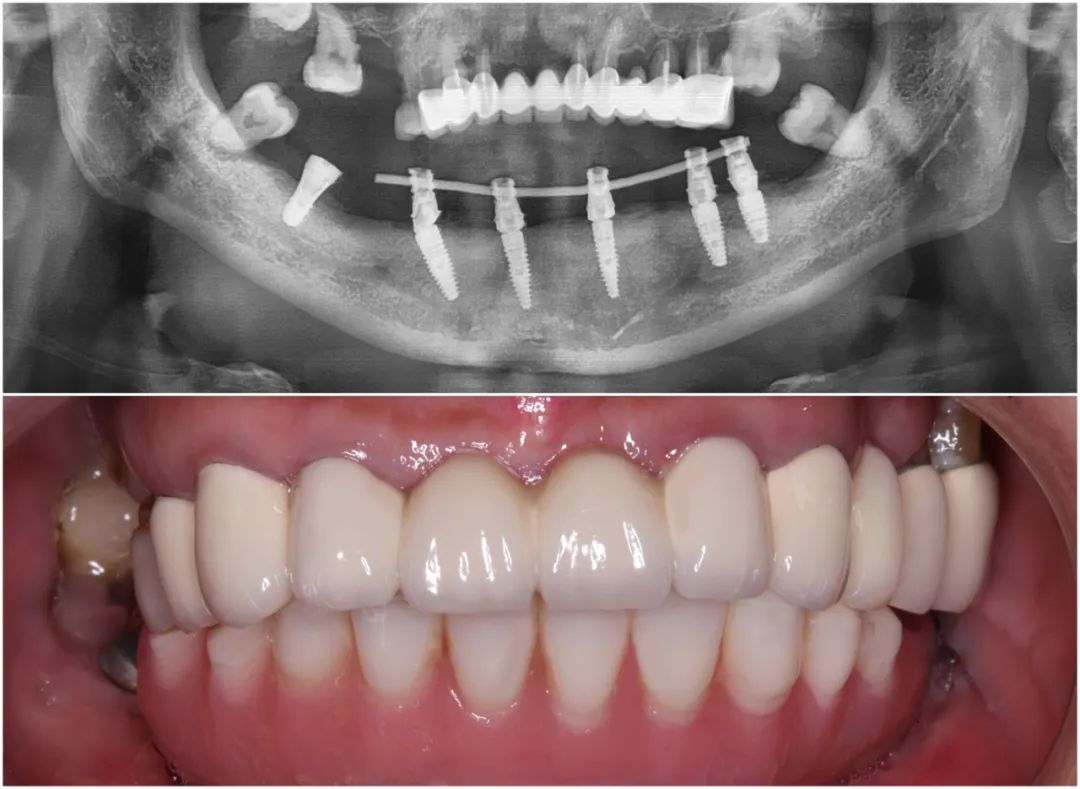

和史阿姨達成共識后,王鋒醫生先為她實施了下半口拔牙和植骨治療。經過大半年的愈合期后,史阿姨牙槽骨量已達臨床種植條件,一次植入6顆植體并戴上臨時牙冠,即刻重拾半口好牙。

史阿姨下頜種牙后全景片及口內照